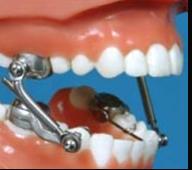

Herbst: Piston sisteminden oluşan rijit bir apareydir. Dişlerin kronlanmasıyla uygulanır.